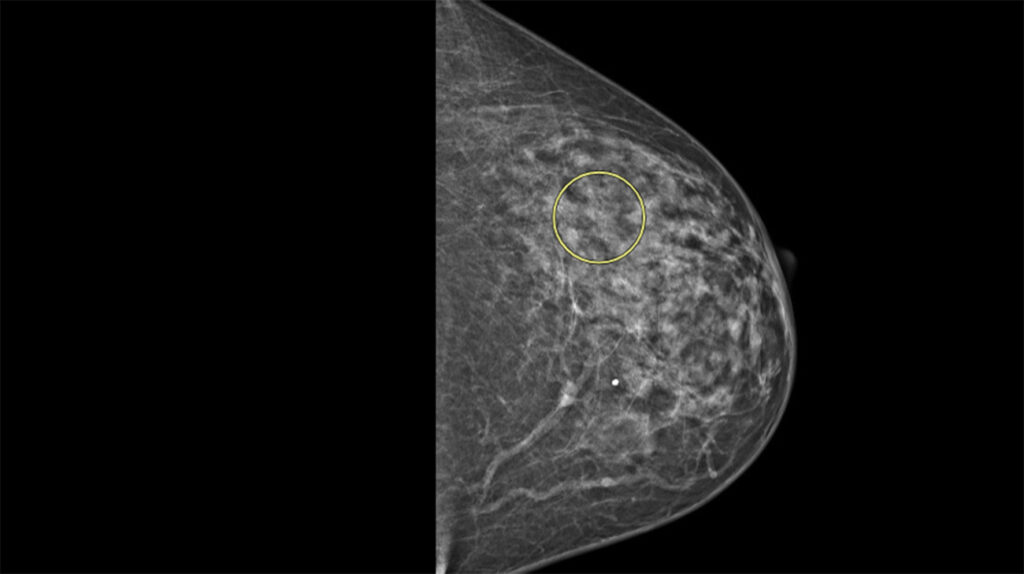

Those tests confirmed Tammy had invasive lobular breast cancer, a form of breast cancer that’s notoriously difficult to detect. Unlike ductal breast cancer, which typically forms noticeable lumps, lobular cancer grows in strands or webs of cells, often blending into surrounding tissue. Though it accounts for up to 15% of invasive breast cancers, it’s often referred to as “the sneaky breast cancer” because it can go unnoticed for longer periods.

In September 2024, her annual screening revealed a subtle anomaly—detected by who she calls an “eagle-eyed radiologist” at Cleveland Clinic. That finding led to two follow-up procedures: a diagnostic mammogram and mammography-guided needle aspiration to collect a tissue sample.